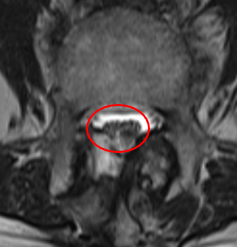

治療後

術後の翌日には足の痛みは軽減。右下肢の痛み、痺れも取れてきて、痺れの範囲は狭くなっているとのことでした。腰痛を含めた痛み、痺れの数値について10から4に。術後に撮った腰椎MRIでも減圧していたことを確認し、採血も問題ありませんでした。